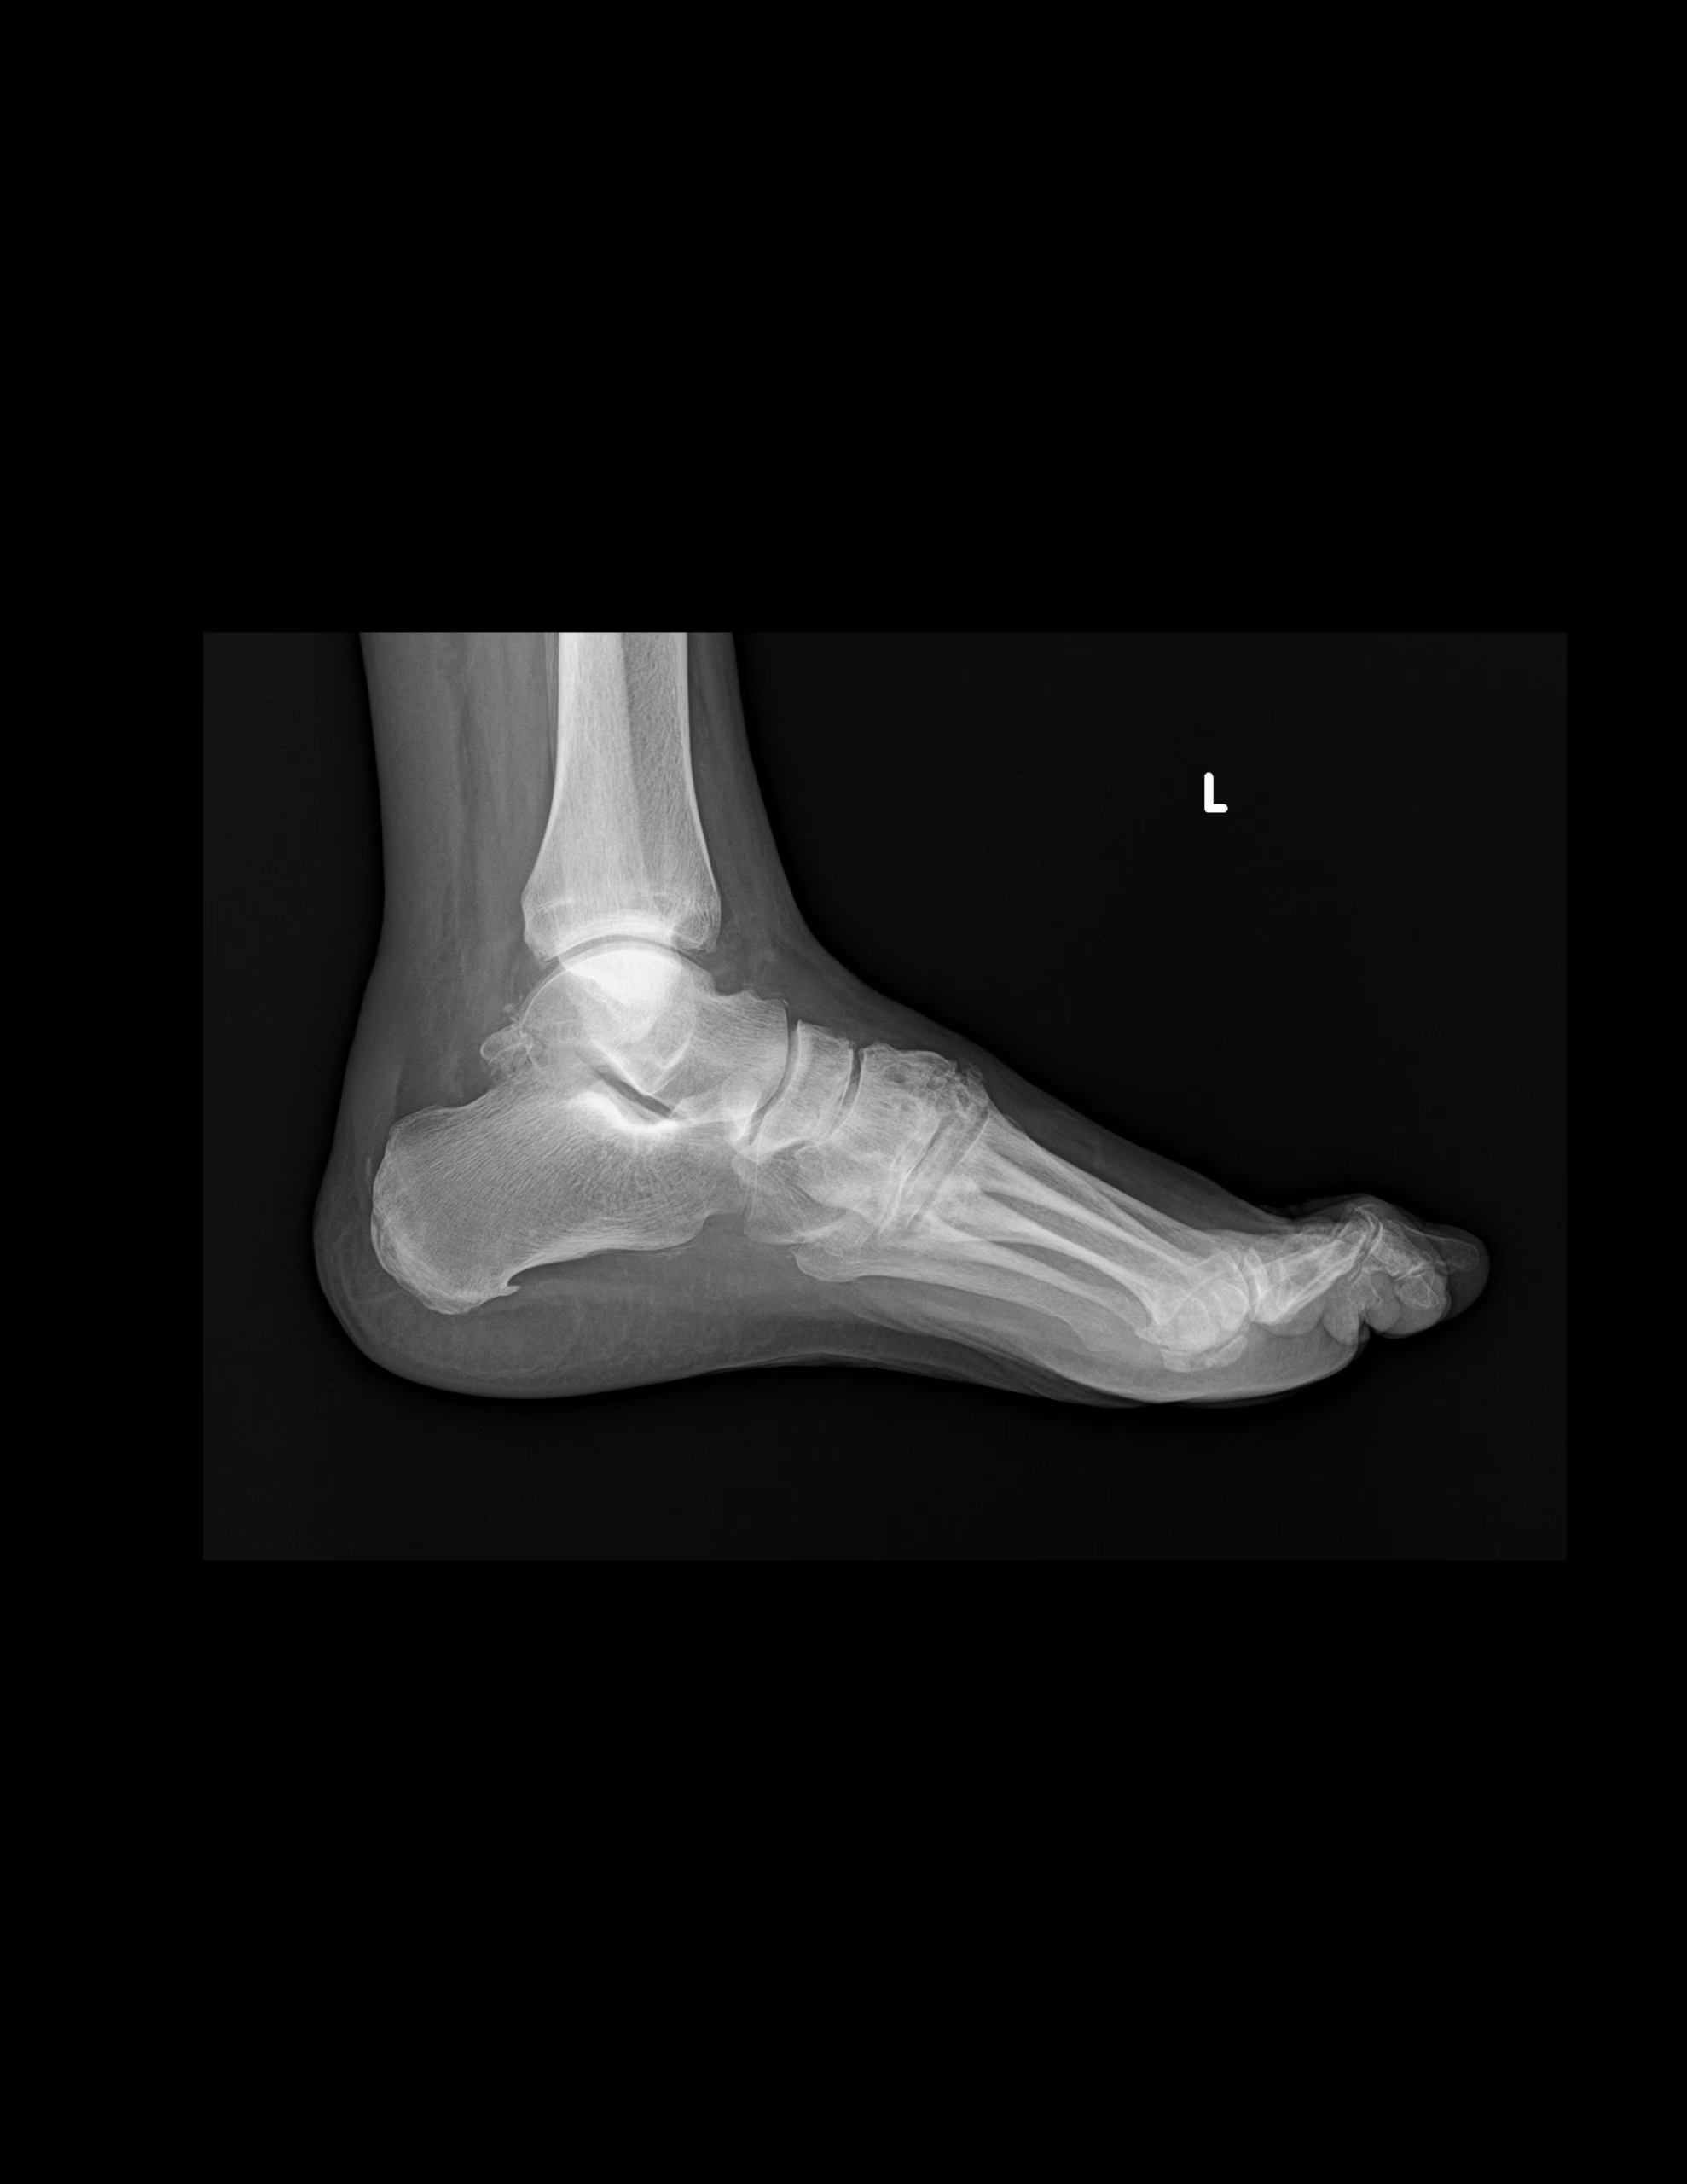

-Tejidos blandos, existe aumento densidad y grosor a nivel posterior.

-Se observa trayecto compuesto a nivel de proceso posterior del astrágalo. 2do cuneiforme con trazo longitudinal no desplazada. A nivel de base de 2do metatarso, con aparente fractura. Existe espícula osteofítica en porción inferior de tuberosidad del calcáneo. Resto de huesos del tarso, metatarsos y falanges, con disminución de la densidad, sin evidencia de lesiones líticas, blásticas o perdidas de la contigüidad.

EXISTE ESPOLÓN ÓSEO DEL CALCÁNEO.